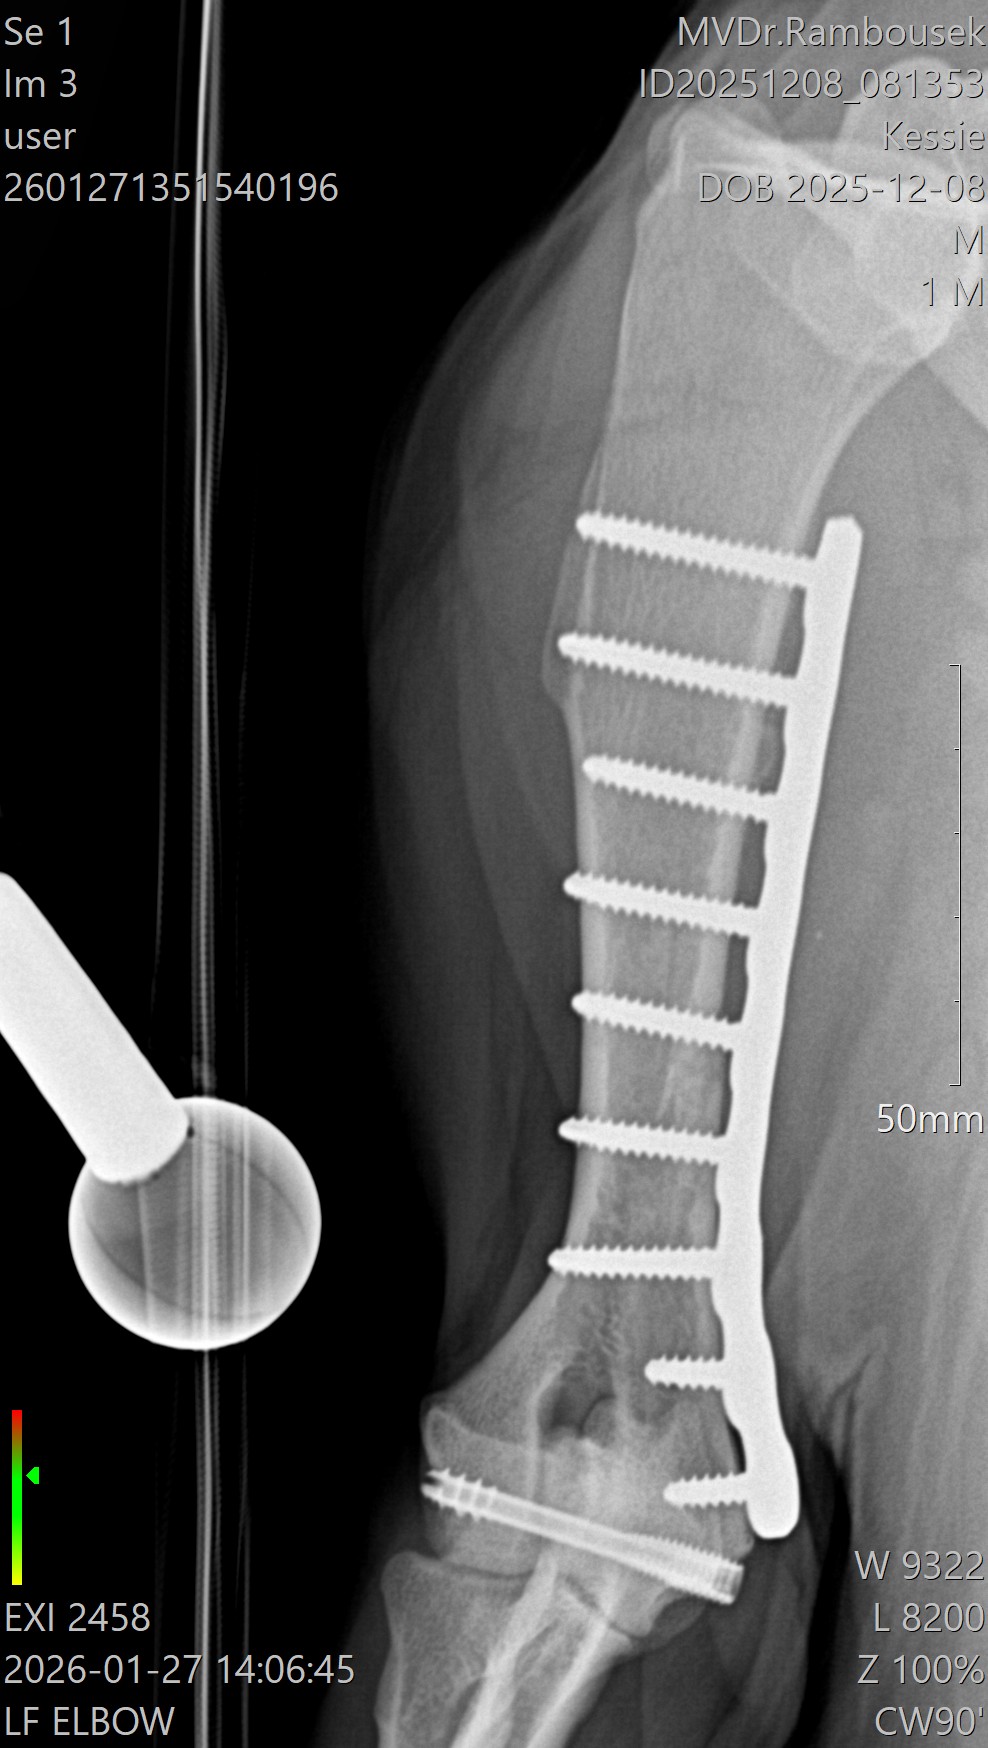

Fraktura pažní kosti - mediální kondylus

Případy z praxe

Akutní

případ